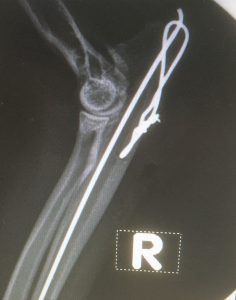

This right articular proximal ulna fracture occurred outside of the house in unknown circumstances about a week before the presentation.

It was reduced and fixed with a pin and tension wire and healed uneventfully. Sometimes we need to remove the implants in these cases after the fracture has healed.